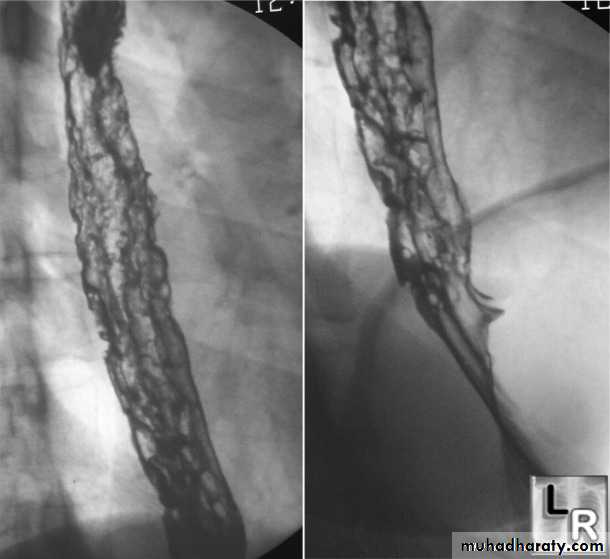

Candida esophagitis is often associated with oral thrush and tends to present with dysphagia and only mild pain on swallowing. It has a characteristic appearance on endoscopy, and esophageal brushings and biopsies demonstrate fungal hyphae. Treatment with oral fluconazole is generally very effective.

Investigations Chest X-ray; widening of the mediastinum, aspiration pneumonia.A barium swallow; tapered narrowing of the lower esophagus, esophageal body is dilated, aperistaltic and food-filled.Endoscopy; must always be carried out, carcinoma of the cardia can mimic the presentation and radiological and manometric features of achalasia ('pseudo-achalasia').Manometry; confirms the high-pressure, non-relaxing lower esophageal sphincter with poor contractility of the esophageal body.

Investigations Endoscopy; The investigation of choice, with cytology and biopsy.Barium swallow ; site and length of the stricture .Thoracic and abdominal CT Endoscopic ultrasound (EUS)